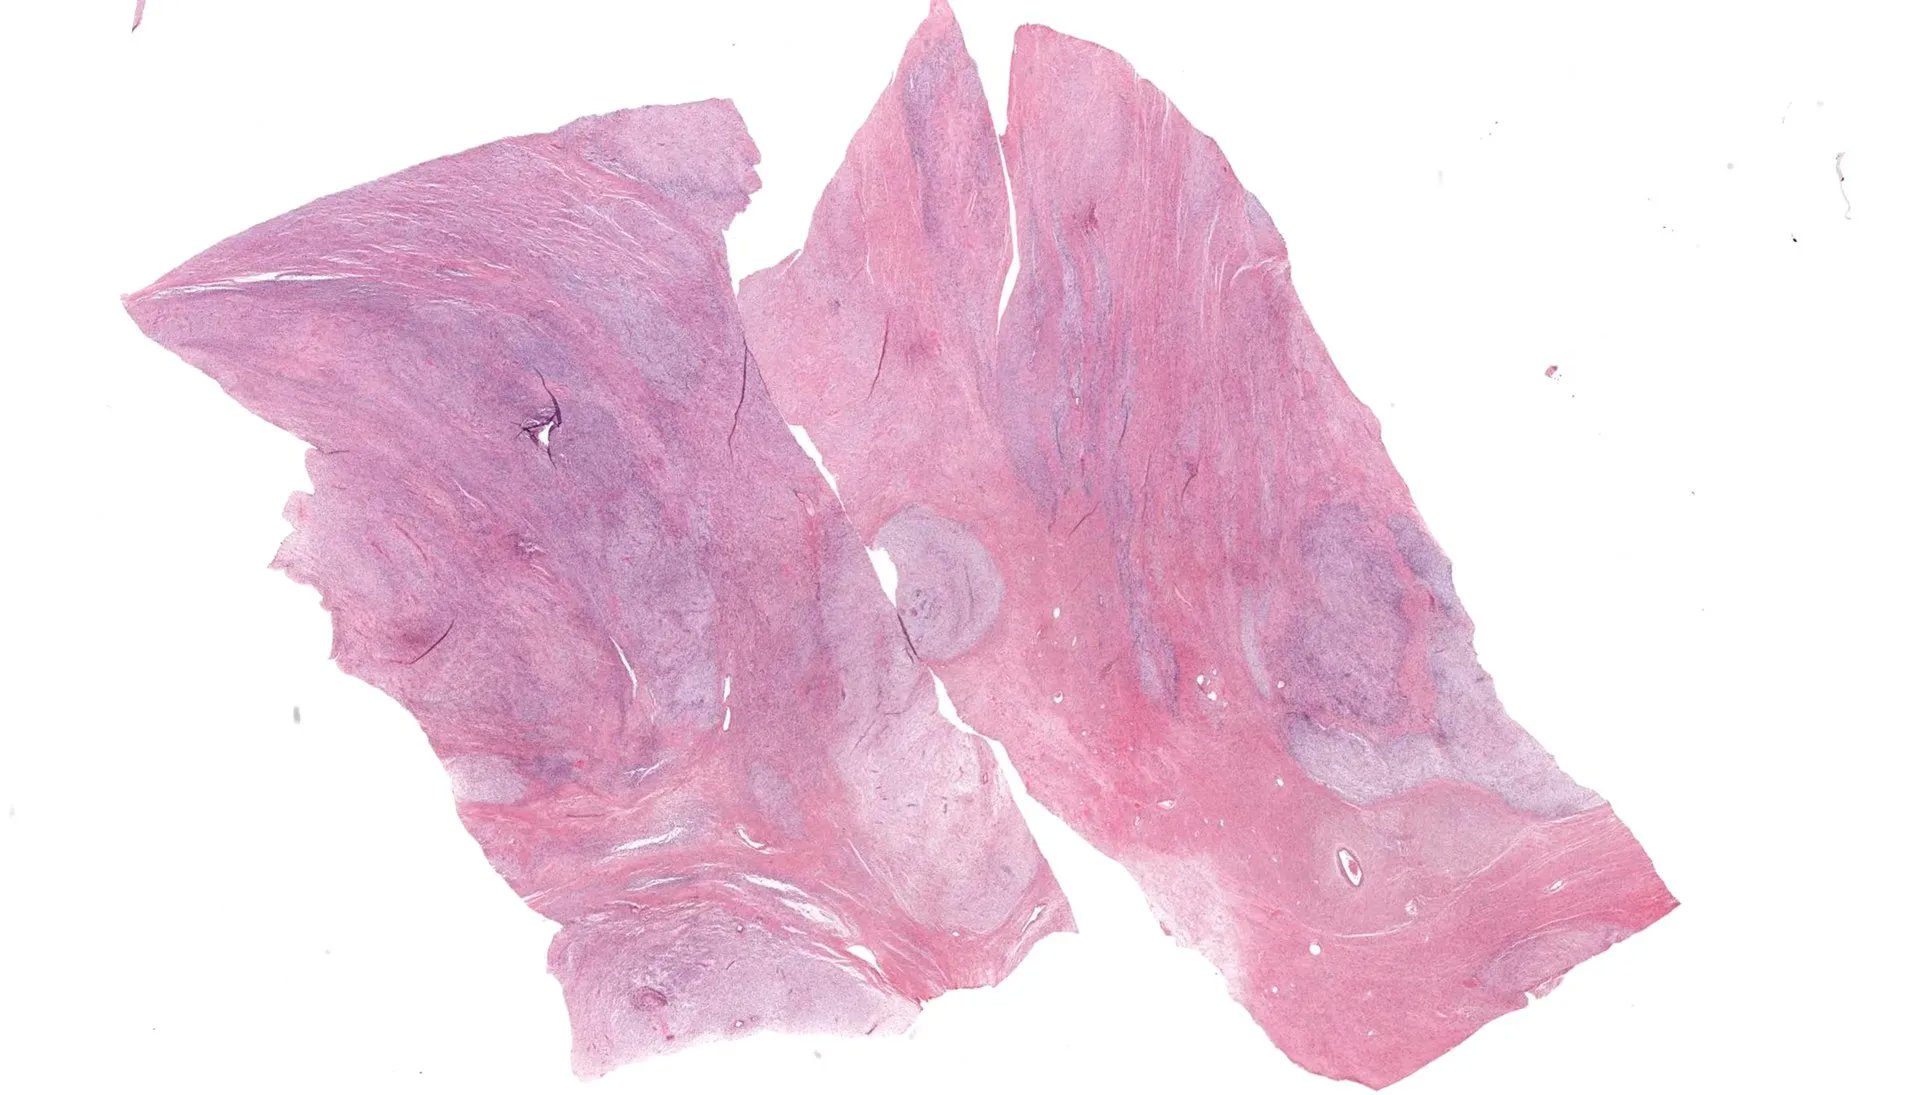

Gross description

- Often large (median ~9 cm), well circumscribed, fibromyxoid cut surface, may be grossly infiltrative

Gross images